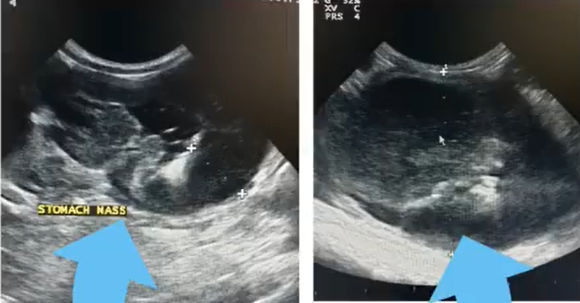

Earlier in the year, Mowgli’s owners noticed that he had gone off his food, and had begun vomiting, and so quickly took him to see Reena at Medivet Pinner. After quickly conducting an ultrasound on Mowgli, Reena discovered a large tumour which was taking up most of the space in his stomach.

Happily, on his last ultrasound scan, the tumour had gone. Mowgli has his appetite back, and now has a belly full of food instead. The team at Medivet Pinner are pleased to say he is now in remission and doing well, and this much-loved little cat had very few side-effects from the chemotherapy and is now living a content and cancer-free life.